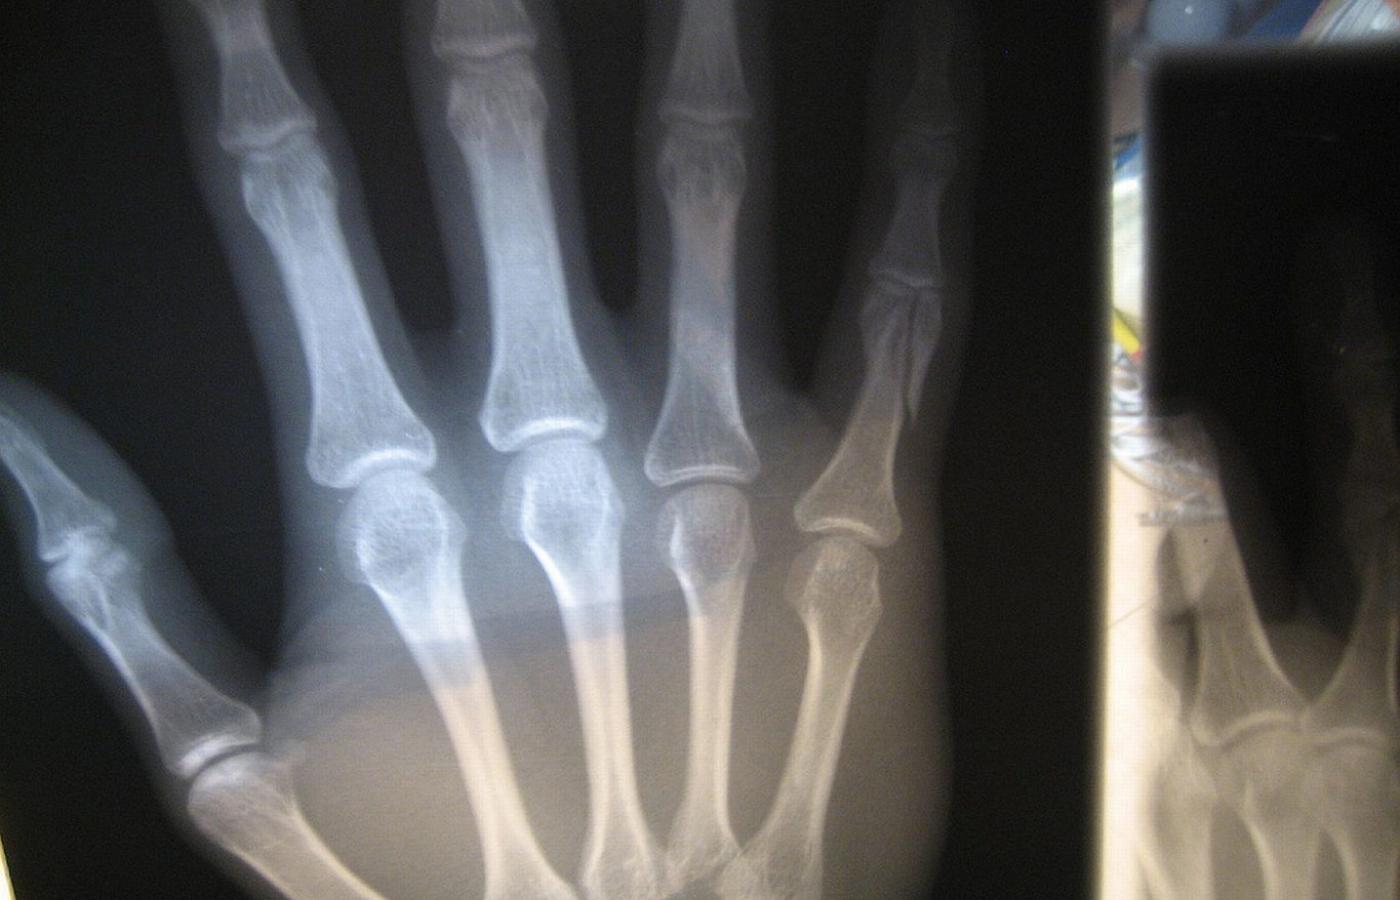

Zagrożenie wynikające z wykonania jednego zdjęcia jest niewielkie, ale z każdą kolejną dawką promieniowania ryzyko dla zdrowia rośnie. Zagrożenie wynikające z wykonania jednego zdjęcia jest niewielkie, ale z każdą kolejną dawką promieniowania ryzyko dla zdrowia rośnie. keone / Flickr CC by SA

Kilkanaście procent skierowań na badania z wykorzystaniem promieniowania rentgenowskiego jest wydawanych na wyrost.Alamy/BEW Kilkanaście procent skierowań na badania z wykorzystaniem promieniowania rentgenowskiego jest wydawanych na wyrost.